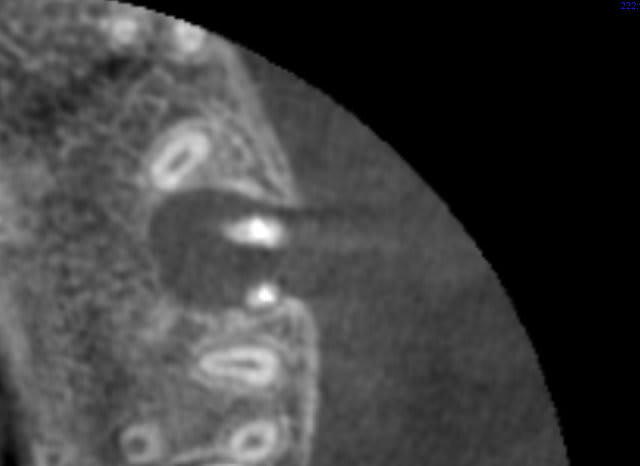

Ok, donc 2 autres coupes axiales:

Mais au bout d'un moment la 3 d montre pas tout: tu peux ne pas voir une lumiere canalaire qui existe dans la dent.

+ l'artefact du gros cone de gutta

(j'ai mis 2 fois la meme : arrive pas à la retirer)

ton canal mésio ves avec commnunication MV1 MV2 est de forme

allongée comme sur la 27 et ton cône de gutta est central

et n'obture pas tout l'apex de façon hermétique (par contre

"bonjour la difficulté d'obturation 3d mac spadden ou système B?)

tout ceci ce sont des interprétations et je pense que le bout de l'apex mésio ves de ta 26 est allongé ;c'est pourquoi on réclame plus de coupes CBCT possible puisque tous les mm et en particulier la coupe du bout des 3 apexs

de ta 26

je pense que la LIPOE vient de la racine mésiale;